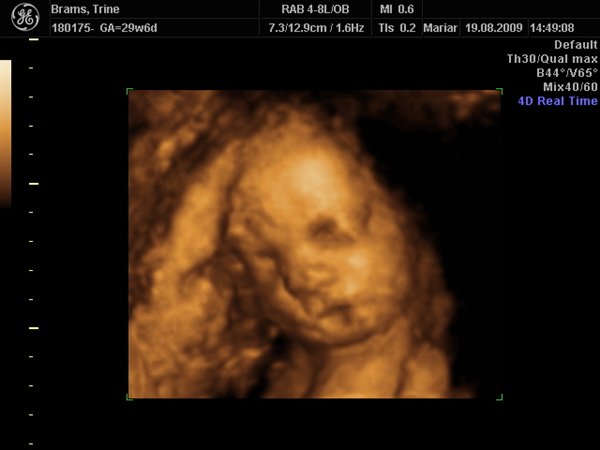

Jeg har lige været til en 3D/4D scanning (27+0), hvilket var en kæmpe oplevelse. Jeg venter en dreng på foreløbig 976 gram

Denne tråd er for alle os som har fået foretaget sådan en scanning. Jeg tænkte det kunne være sjovt at smide nogle fotos op af vores bebzere, da de lå i maven. I profil og forfra.

Skriv gerne hvilken uge scanningen er foretaget, samt evt. hvad køn det er